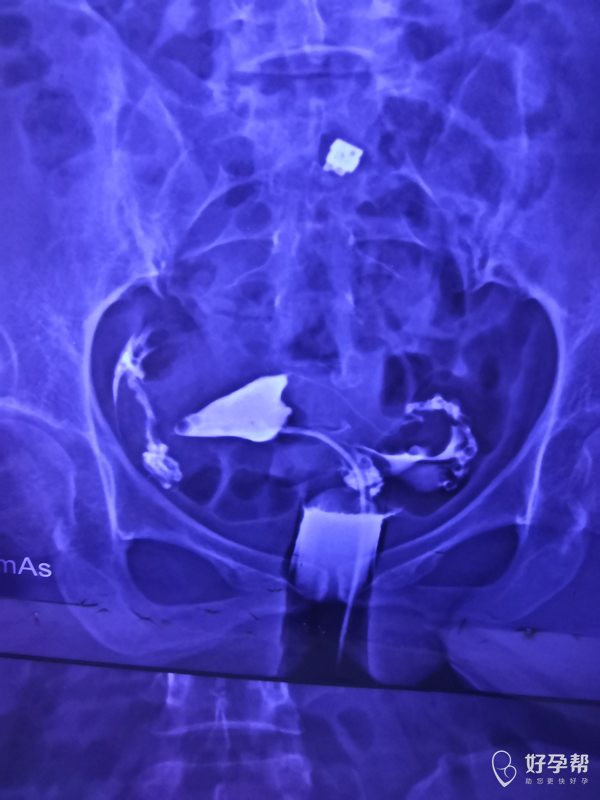

输卵管通而不畅伞端粘连试管三次未成后续是试管